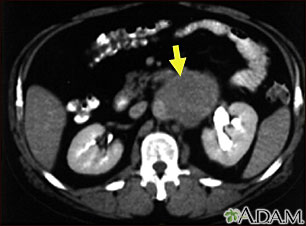

A needle biopsy involves inserting a needle into a lymph node. This type of biopsy can be performed by a radiologist with local anesthesia, using ultrasound or CT scan to find the node. It can also be performed by a surgeon without imaging if the lymph node can be felt.

- When abnormal lymph nodes are present on a mammogram, ultrasound, CT, or MRI scan